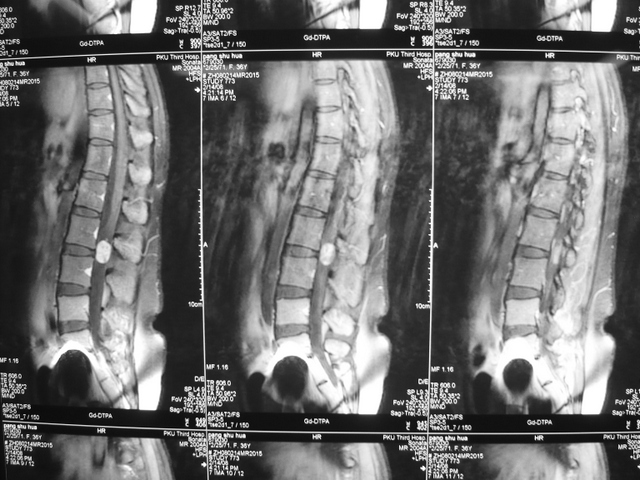

腰椎管内神经鞘瘤

P1030144.JPGP1030138.JPG

P1030146.JPG